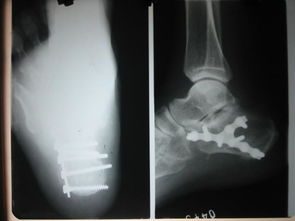

我家狗狗一歲之前前腿骨折, 拍片和你這個(gè)情況看起來差不多. 沒有做麻醉和內(nèi)固定手術(shù). 做的是外固定, 不過做好外固定以后就要注意補(bǔ)鈣, 一個(gè)月左右, 就好了. 平時(shí)要看好它. 不能讓它亂動(dòng), 特別是睡覺之前要確定它能正常躺下, 躺下和站起來的過程是比較痛的. 小狗的恢復(fù)能力比人強(qiáng)很多, 他們的代謝速度是我們的好幾倍. 所以也不需要太擔(dān)心了. 但是如果一定要做手術(shù)的話, 鋼針一定要取出來的. 至于麻藥的風(fēng)險(xiǎn), 不能說沒有. 我家的做絕育手術(shù)也用了全身麻醉, 有各別狗狗會(huì)有過敏性休克. 但是幾率很低.至于這個(gè)南瓜子,我沒有喂過. 不過如果是我要喂狗狗吃的話, 應(yīng)該會(huì)磨碎或者弄小顆拌狗糧, 它就會(huì)吃. 我家的是吃貨, 不挑食的. 假如挑食的話, 可以稍微烤一下嘛, 香一點(diǎn)自然會(huì)吃啦! 其實(shí)狗狗真的好的很快的. 最主要的是看好它不要讓它亂動(dòng)重復(fù)受傷, 如果接好了以后固定住了又錯(cuò)位, 就很麻煩了. 還有接不好或者又亂動(dòng)錯(cuò)位了還給長好了, 就很可能變成長短腿或者Z型腿. 如果對(duì)你有幫助記得采納哦。

看了你追加描述和圖片,基本確定是骨折!不打算去醫(yī)院的話就按照我上面說的做,狠狠心找到骨折的地方,試著做一下整復(fù),外邊用硬紙殼固定!可以去買一些人藥!狗狗會(huì)很快好起來的